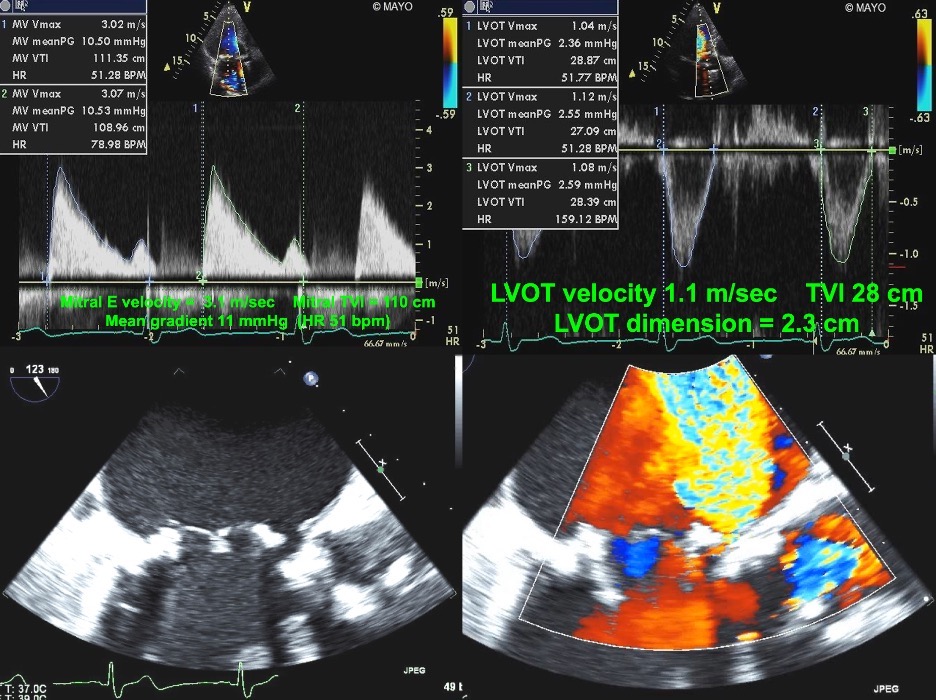

Fig. 7.Echocardiographic imaging of a patient with a mitral bioprosthesis and heart failure symptoms found to have prosthetic thrombosis.

Top Left: Continuous Wave Doppler in a patient with a

31 mm Hancock porcine mitral bioprosthesis who presented with dyspnea on exertion

and lightheadedness. The mean gradient was 12 mmHg with a heart rate of 51 and a

pressure halftime of 280 msec. The DVI was 5.7, with an EOAi of 0.44

cm

Fig. 8.Echocardiographic imaging of a patient with a mitral bioprosthesis and prosthetic dehiscence. Top Left and Right: Continuous Wave Doppler of a male

with a Biocor porcine mitral bioprosthesis just 5 months previously. The mean

gradient was 11 mmHg with a heart rate of 51. The DVI was 4.0, with an EOAi of

0.48 cm